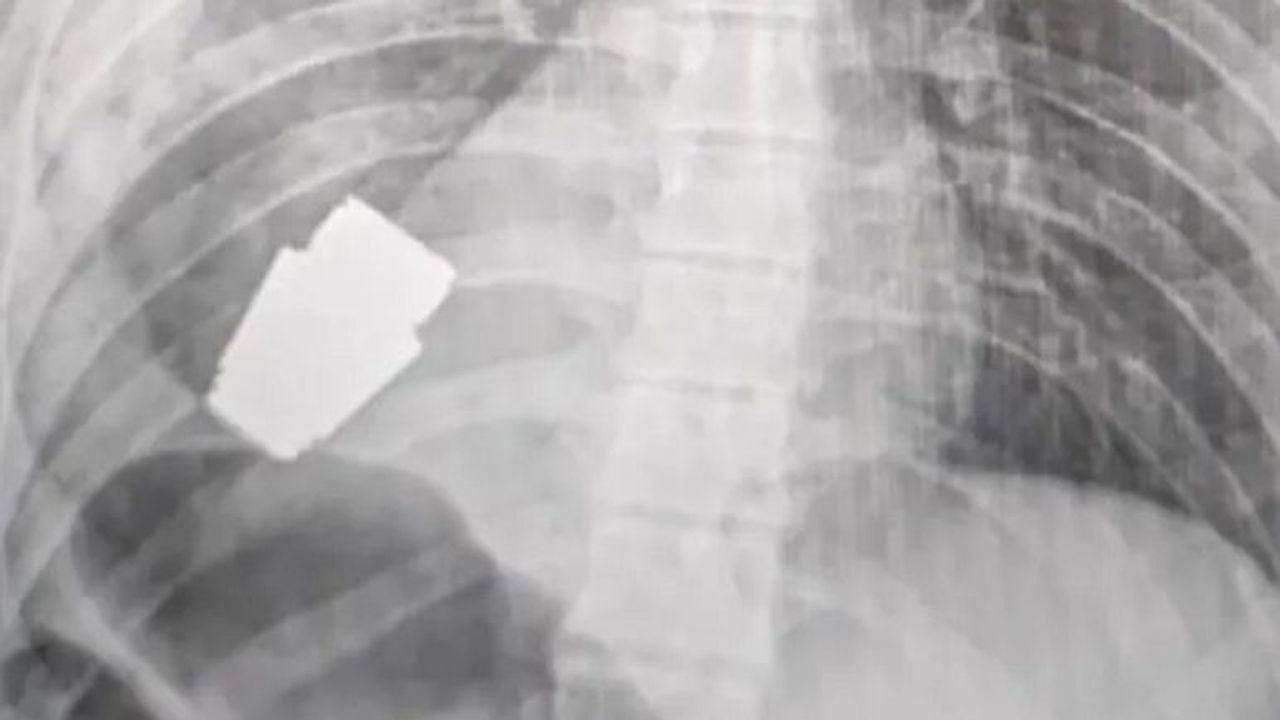

Bombanın röntgen filmini paylaşan Ukrayna Savunma Bakan Yardımcısı Hanna Maliar, cerrahların bombayı yaralı askerin kalbinin hemen altında bulunduğu noktadan çıkardığını, iki istihkam erinin de operasyonun güvenli bir şekilde yürütülmesini sağladığını aktardı.

Maliar, Facebook'tan yaptığı paylaşımda "Askeri cerrahlar, askerin vücudundan infilak etmemiş bir VOG el bombasını çıkarmak için operasyon gerçekleştirdi" ifadesini kullandı.

Maliar, operasyonun ameliyat sırasında kanamayı kontrol etmek için elektrokoagülasyon kullanılmadan gerçekleştirildiğini zira "el bombasının her an patlama" riskinin olduğunu söyledi.